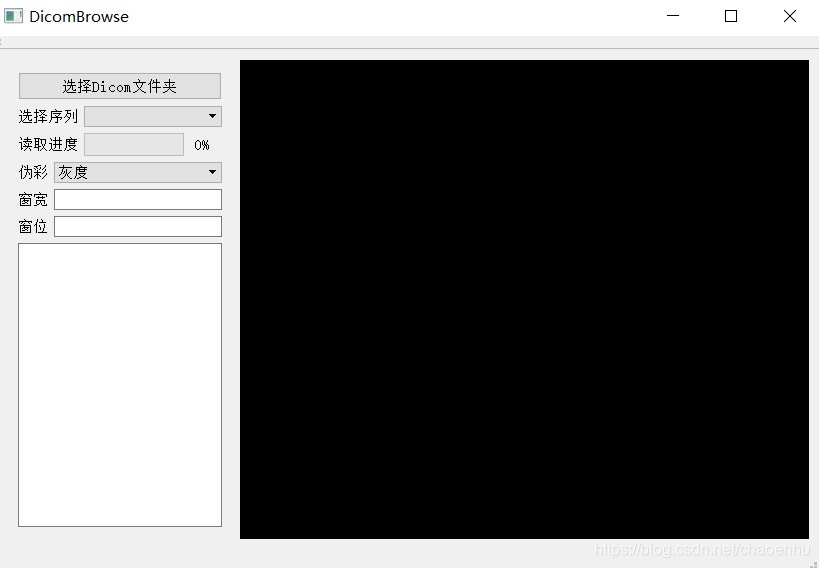

二、提升UI文件QGraphicsView 为 DicomView

保存提升后的ui,运行调试,就会发现显示框变黑了,提升成功。